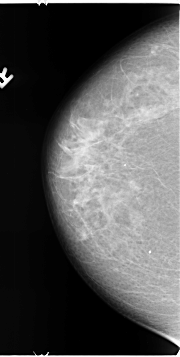

B_3123_1.LEFT_MLO

LEFT_MLO LINES 4696 PIXELS_PER_LINE 2680 BITS_PER_PIXEL 12 RESOLUTION 50 OVERLAY